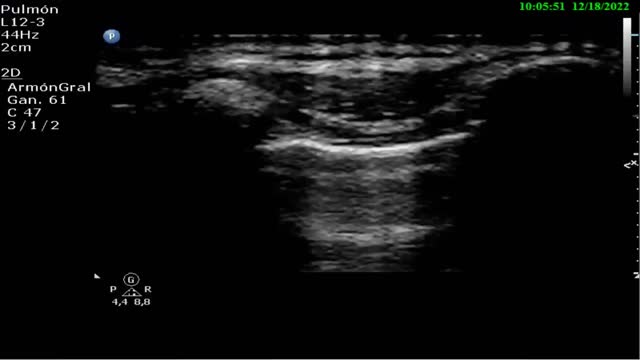

PneumothoraxWhen pneumothorax is suspected, ultrasound proves especially relevant in clinical scenarios such as chest traumatism, barotrauma associated with mechanical ventilation (MV), following central venous access catheterization, and in patients that are to be transferred by air. These situations can be found in a critical patients area or in an emergency service, where an ultrasound system preferably with a linear probe (7.5-12 MHz) should be available, in order to discard the presence of pneumothorax.

Related ultrasound signsThe following ultrasound findings are to be considered for detecting or discarding the presence of air in the pleural cavity (Suppl. Table 1)19:

A lines (Fig. 4): These indicate the presence of air in the chest. This finding is always present in the diagnosis of pneumothorax.

Absence of “lung sliding”: In the event of pneumothorax, pleural sliding disappears (Video 2), since the presence of gas (air) separates the two pleural layers. This finding is not pathognomonic of pneumothorax, as it can also be found in situations where the lung is not aerated (selective and esophageal intubations or atelectasis). The presence of pleural sliding discards pneumothorax with a negative predictive value and sensitivity of 100%.2 In the combined presence of A-lines and the absence of sliding, the sensitivity reaches 100% and specificity 96%.2